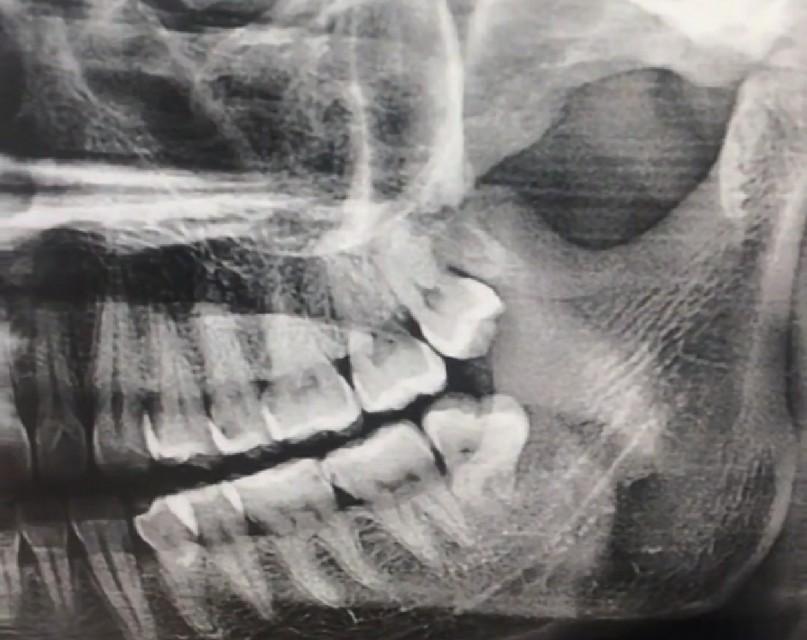

下顎的智齒拔起來(lái)可以說(shuō)相當(dāng)?shù)睦щy,它有逆生長(zhǎng)的、壓根不露頭的、還有牙根帶鉤的、關(guān)鍵是下顎接近腦神經(jīng),拔下額的智齒必須要拍牙齒圖片,拍一個(gè)圖片也就50塊錢左右,如果圖片出來(lái)智齒的位置比較麻煩,好還是多花點(diǎn)錢去三甲醫(yī)院拔除,下顎智齒拔除的困難度不同價(jià)格也不同,有的隱藏智齒需要開(kāi)刀縫合切割,長(zhǎng)時(shí)間甚至需要醫(yī)生一個(gè)多小時(shí)的折騰,三甲醫(yī)院的價(jià)格從800到2000也就不奇怪了。